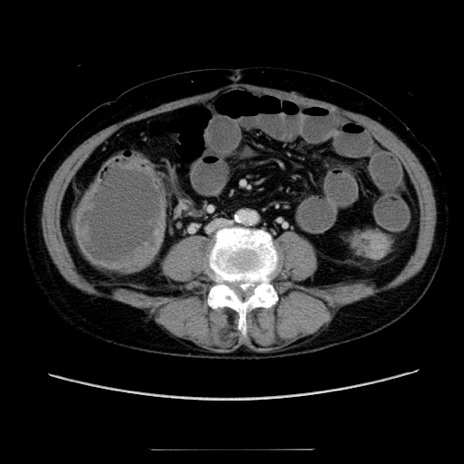

症例5(横断像)

【症例】70歳代女性

【主訴】お腹が張る

【現病歴】1週間くらい前から腹部膨満の自覚あり。昨日夜から増悪したため、本日救急外来受診。

【身体所見】意識清明、BT 36.5℃、BP 165/106mmHg、HR 80bpm、SpO2 98%、腹部:膨満、軟、自発痛・圧痛なし、触診にて不快感あり、腸蠕動音:減弱

【データ】WBC 12600、CRP 1.04